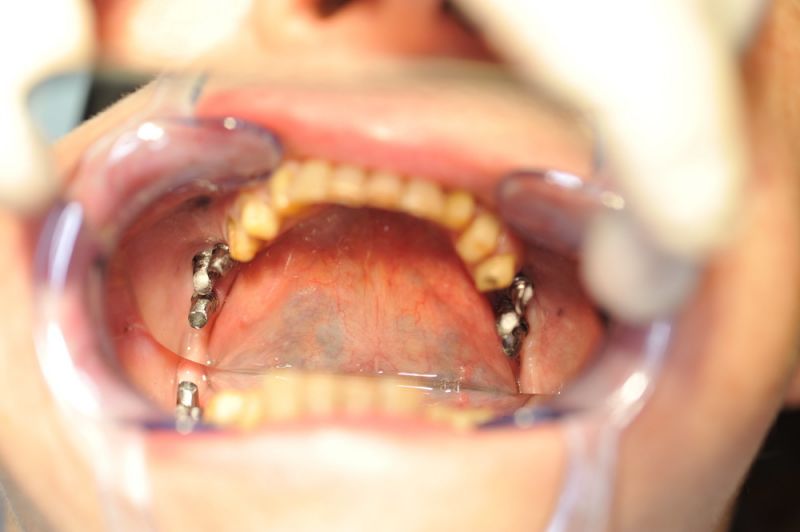

1. Notwendigkeit einer implantatgestützten Kronenversorgung mit der Vorgeschichte, dass die Patientin eine Vielzahl von Behandlern aufgesucht hatte, die eine Implantation im Unterkiefer als nicht durchführbar einschätzten.

2. Extrem schlechte knöcherne Verhältnisse im Unterkieferseitenzahnbereich, die sich intraoperativ noch einmal als ungünstiger darstellten, als bereits in den Voruntersuchungen erkennbar.

3. Sehr dünne Implantate, die von ursprünglich zwei je Kieferhälfte auf letztendlich drei je Kieferhälfte umgeplant werden mussten.

4. Notwendigkeit die Mundhygienefähigkeit der Arbeit auch unter sehr beengten Verhältnissen zu schaffen, um der Arbeit eine günstige Prognose mitzugeben.